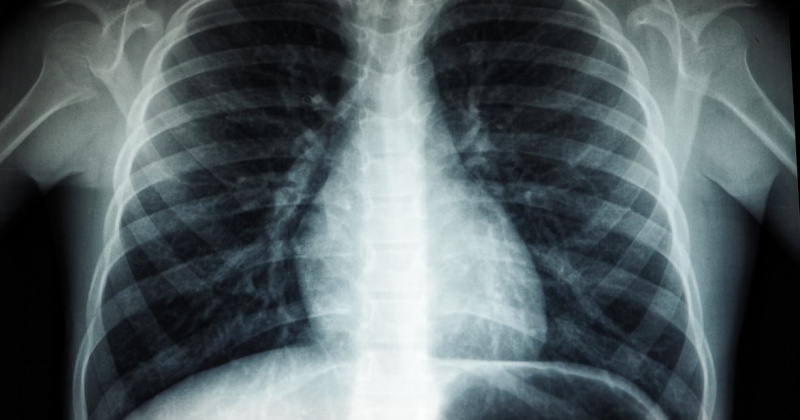

Двое осужденных после отбытия наказания и освобождения из мест лишения свободы отказались в добровольном порядке проходить медицинский осмотр на предмет наличия признаков заболевания туберкулезом.

По искам надзорного ведомства суд обязал граждан пройти медобследование.